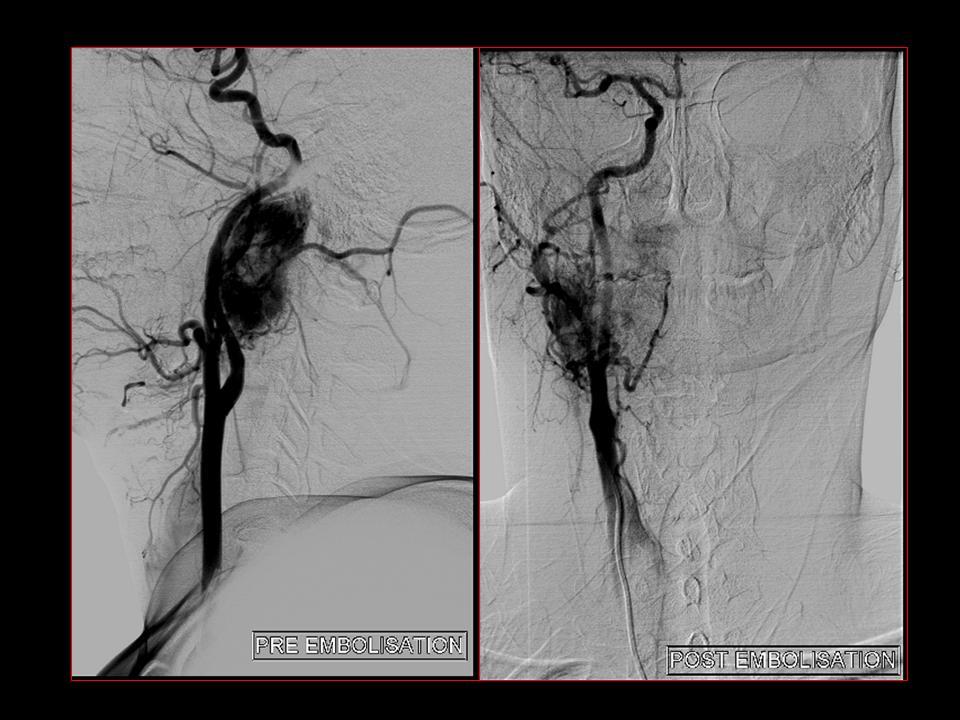

Glomus vagale tumours are paragangliomas that occur along the path of the vagus nerve (CN X). They are a subset of extra-adrenal neuroendocrine tumours that are derived from the nonchromaffin paraganglion cells.

Typically presents as a painless mass behind the carotid artery. Vocal cord paralysis is a relatively frequent finding (~47%) 3.

Although they could occur at a similar position to carotid body tumours they tend to be more rostral in location and do not widen the carotid bifurcation. They displace the internal and external carotid arteries anteriorly, and the internal jugular vein posteriorly 1.